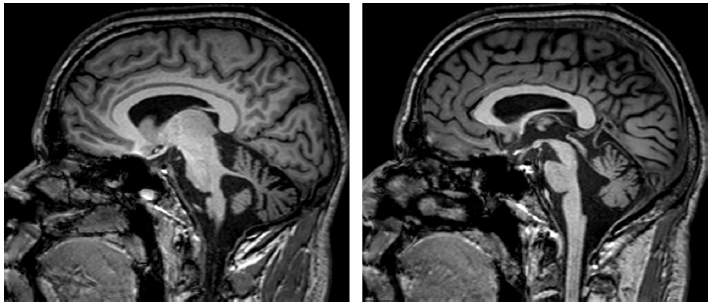

表5总结了四种遗传性共济失调,这四种遗传性共济失调均很常见小脑萎缩。图9显示的是痉挛性共济失调相关的小脑萎缩。图10显示的是线粒体疾病相关的小脑萎缩。运动障碍如震颤和Kayser-Fleischer环的存在应考虑Wilson病(图11)。大多数SCA可见进行性橄榄小脑萎缩(图12和13)。

图9 头颅MRI显示痉挛性共济失调(ARSACS

)相关的小脑萎缩。左:头颅MRI T2加权序列冠状位图像; 右:头颅MRI T1加权序列矢状位图像。

图10 线粒体疾病相关的小脑萎缩。图为头颅MRI T1加权序列矢状位图像。

图11 Wilson病患者头颅MRI 影像。头颅MRI FLAIR序列显示Wilson病中的顶盖和小脑中脚的高信号(箭头)。

图12 患者头颅MRI 影像。头颅MRI T1加权序列显示脊髓小脑性共济失调2型(SCA2)相关的小脑萎缩。脑桥稍扁平(箭头,左侧)和小脑扁桃体保留(箭头,右侧)。

图13 患者头颅MRI 影像。头颅MRI T1加权序列矢状位图像显示脊髓小脑性共济失调2型相关的小脑和脑干萎缩。脑萎缩和脑桥扁平(箭头);可能的脊髓变细。